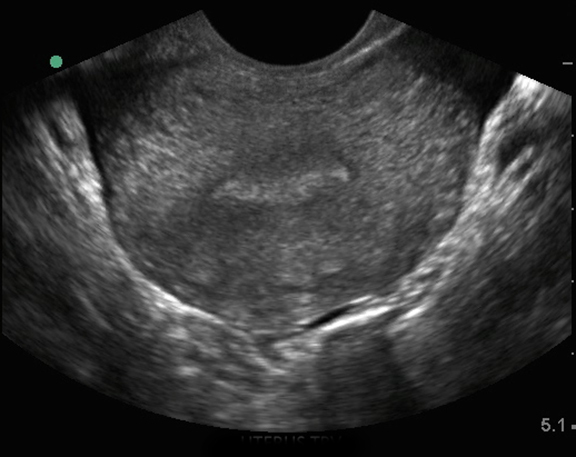

盆腔阴道内子宫:子宫横切面 1 图像

子宫横切面